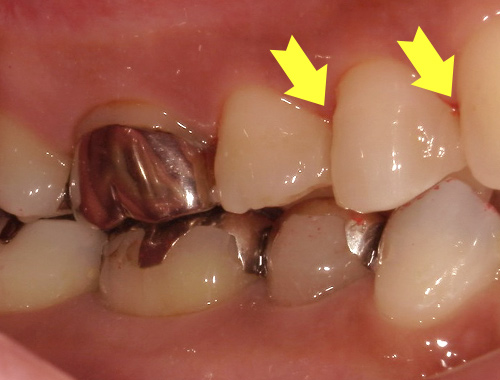

- 症例紹介

保険の被せ物をセラミック

(自費治療)に変更

保険診療で使われていた金属の被せ物を、自然な見た目のセラミッククラウンに変更した症例です。金属の被せ物は、強度が高く保険適用で治療できる一方で、見た目が目立ってしまったり、経年劣化により歯ぐきの黒ずみが出てくることがあります。

今回の症例では、金属の被せ物をセラミックに置き換えることで、まわりの歯と調和のとれた自然な色と形に仕上げました。口元の印象が大きく変わり、笑ったときにも金属が見えず、清潔感のある印象になります。

セラミックは金属を使わない素材のため、金属アレルギーの心配がなく、長期間の使用でも変色しにくいという特長があります。適合性も高く、歯とのすき間ができにくいため、むし歯の再発リスクも軽減されます。

銀歯の見た目が気になる方や、より自然で美しい仕上がりを求める方には、セラミックによる被せ物の治療をおすすめしています。気になることがあれば、まずはお気軽にご相談ください。

治療期間通院3回(むし歯治療、型取り、セット)、約3週間程度

費用目安税込132,000円